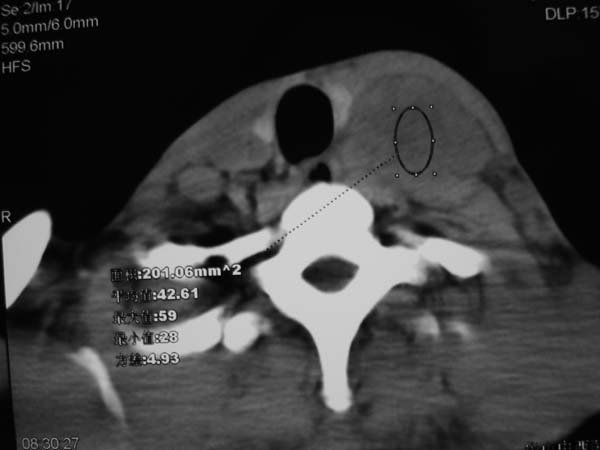

患者男性,37岁,农民,自觉左颈部肿大三天,无其它不适。

左侧颈部软组织密度肿块,界限清楚,形态不规则,占位效应明显。考虑:1 淋巴瘤。2 神经源性肿瘤不除外。

病灶边界较清,密度不均,其内可见坏死灶,左侧甲状腺受压,考虑神经源性肿瘤可能性大,建议穿刺活检。

病灶边界较清,密度不均,其内可见坏死灶,左侧甲状腺受压,考虑神经源性肿瘤可能性大。